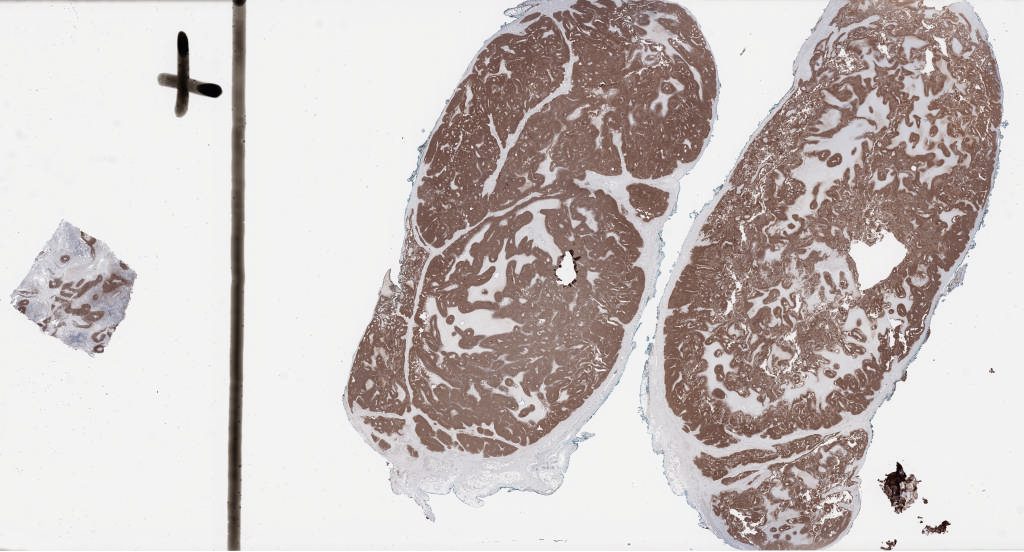

1349182.svs

173304

x

93396

@

40X